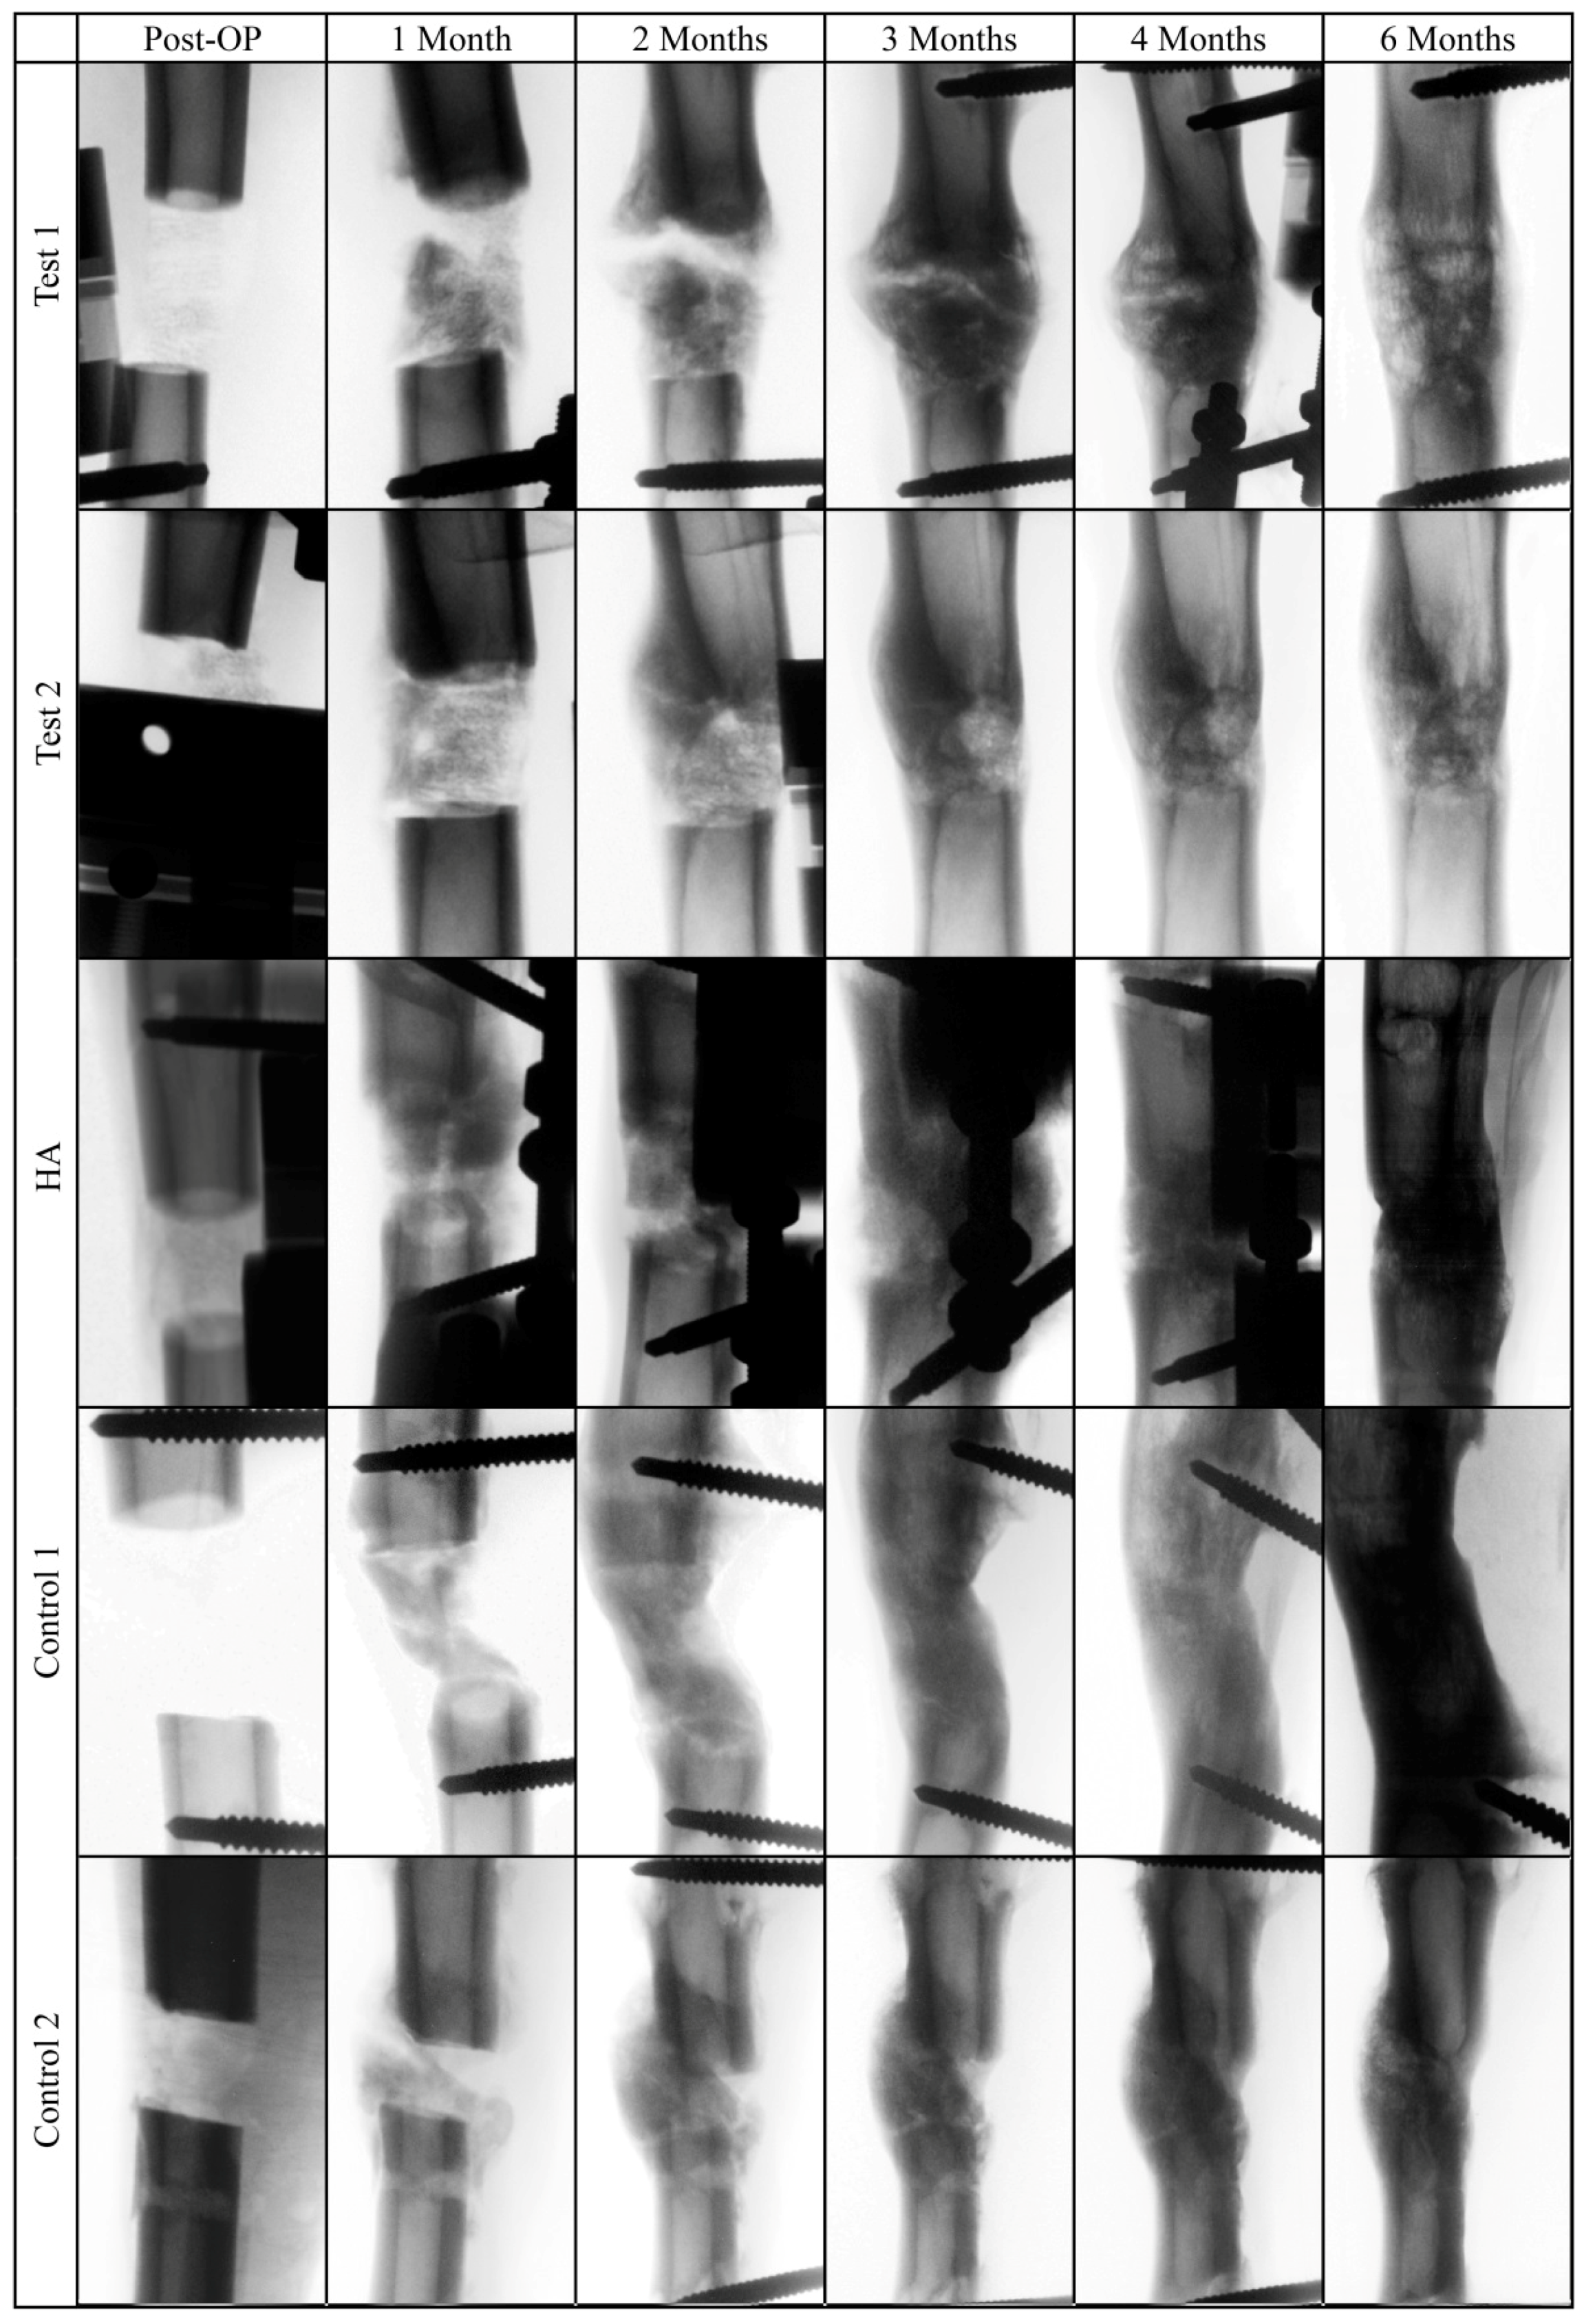

2.6. X-Ray Analysis

The images of the bone defect area revealed comparable radiographic signs of profound new bone formation and bridging of the defect site after six months (Figure 4). Increased callus formation could be observed in the test group after two, three, and four months, which completely disappeared after five months.

Figure 4.

Representative invers radiograph images of the tibial bone defect area after surgery and after one, two, three, four, and six months.